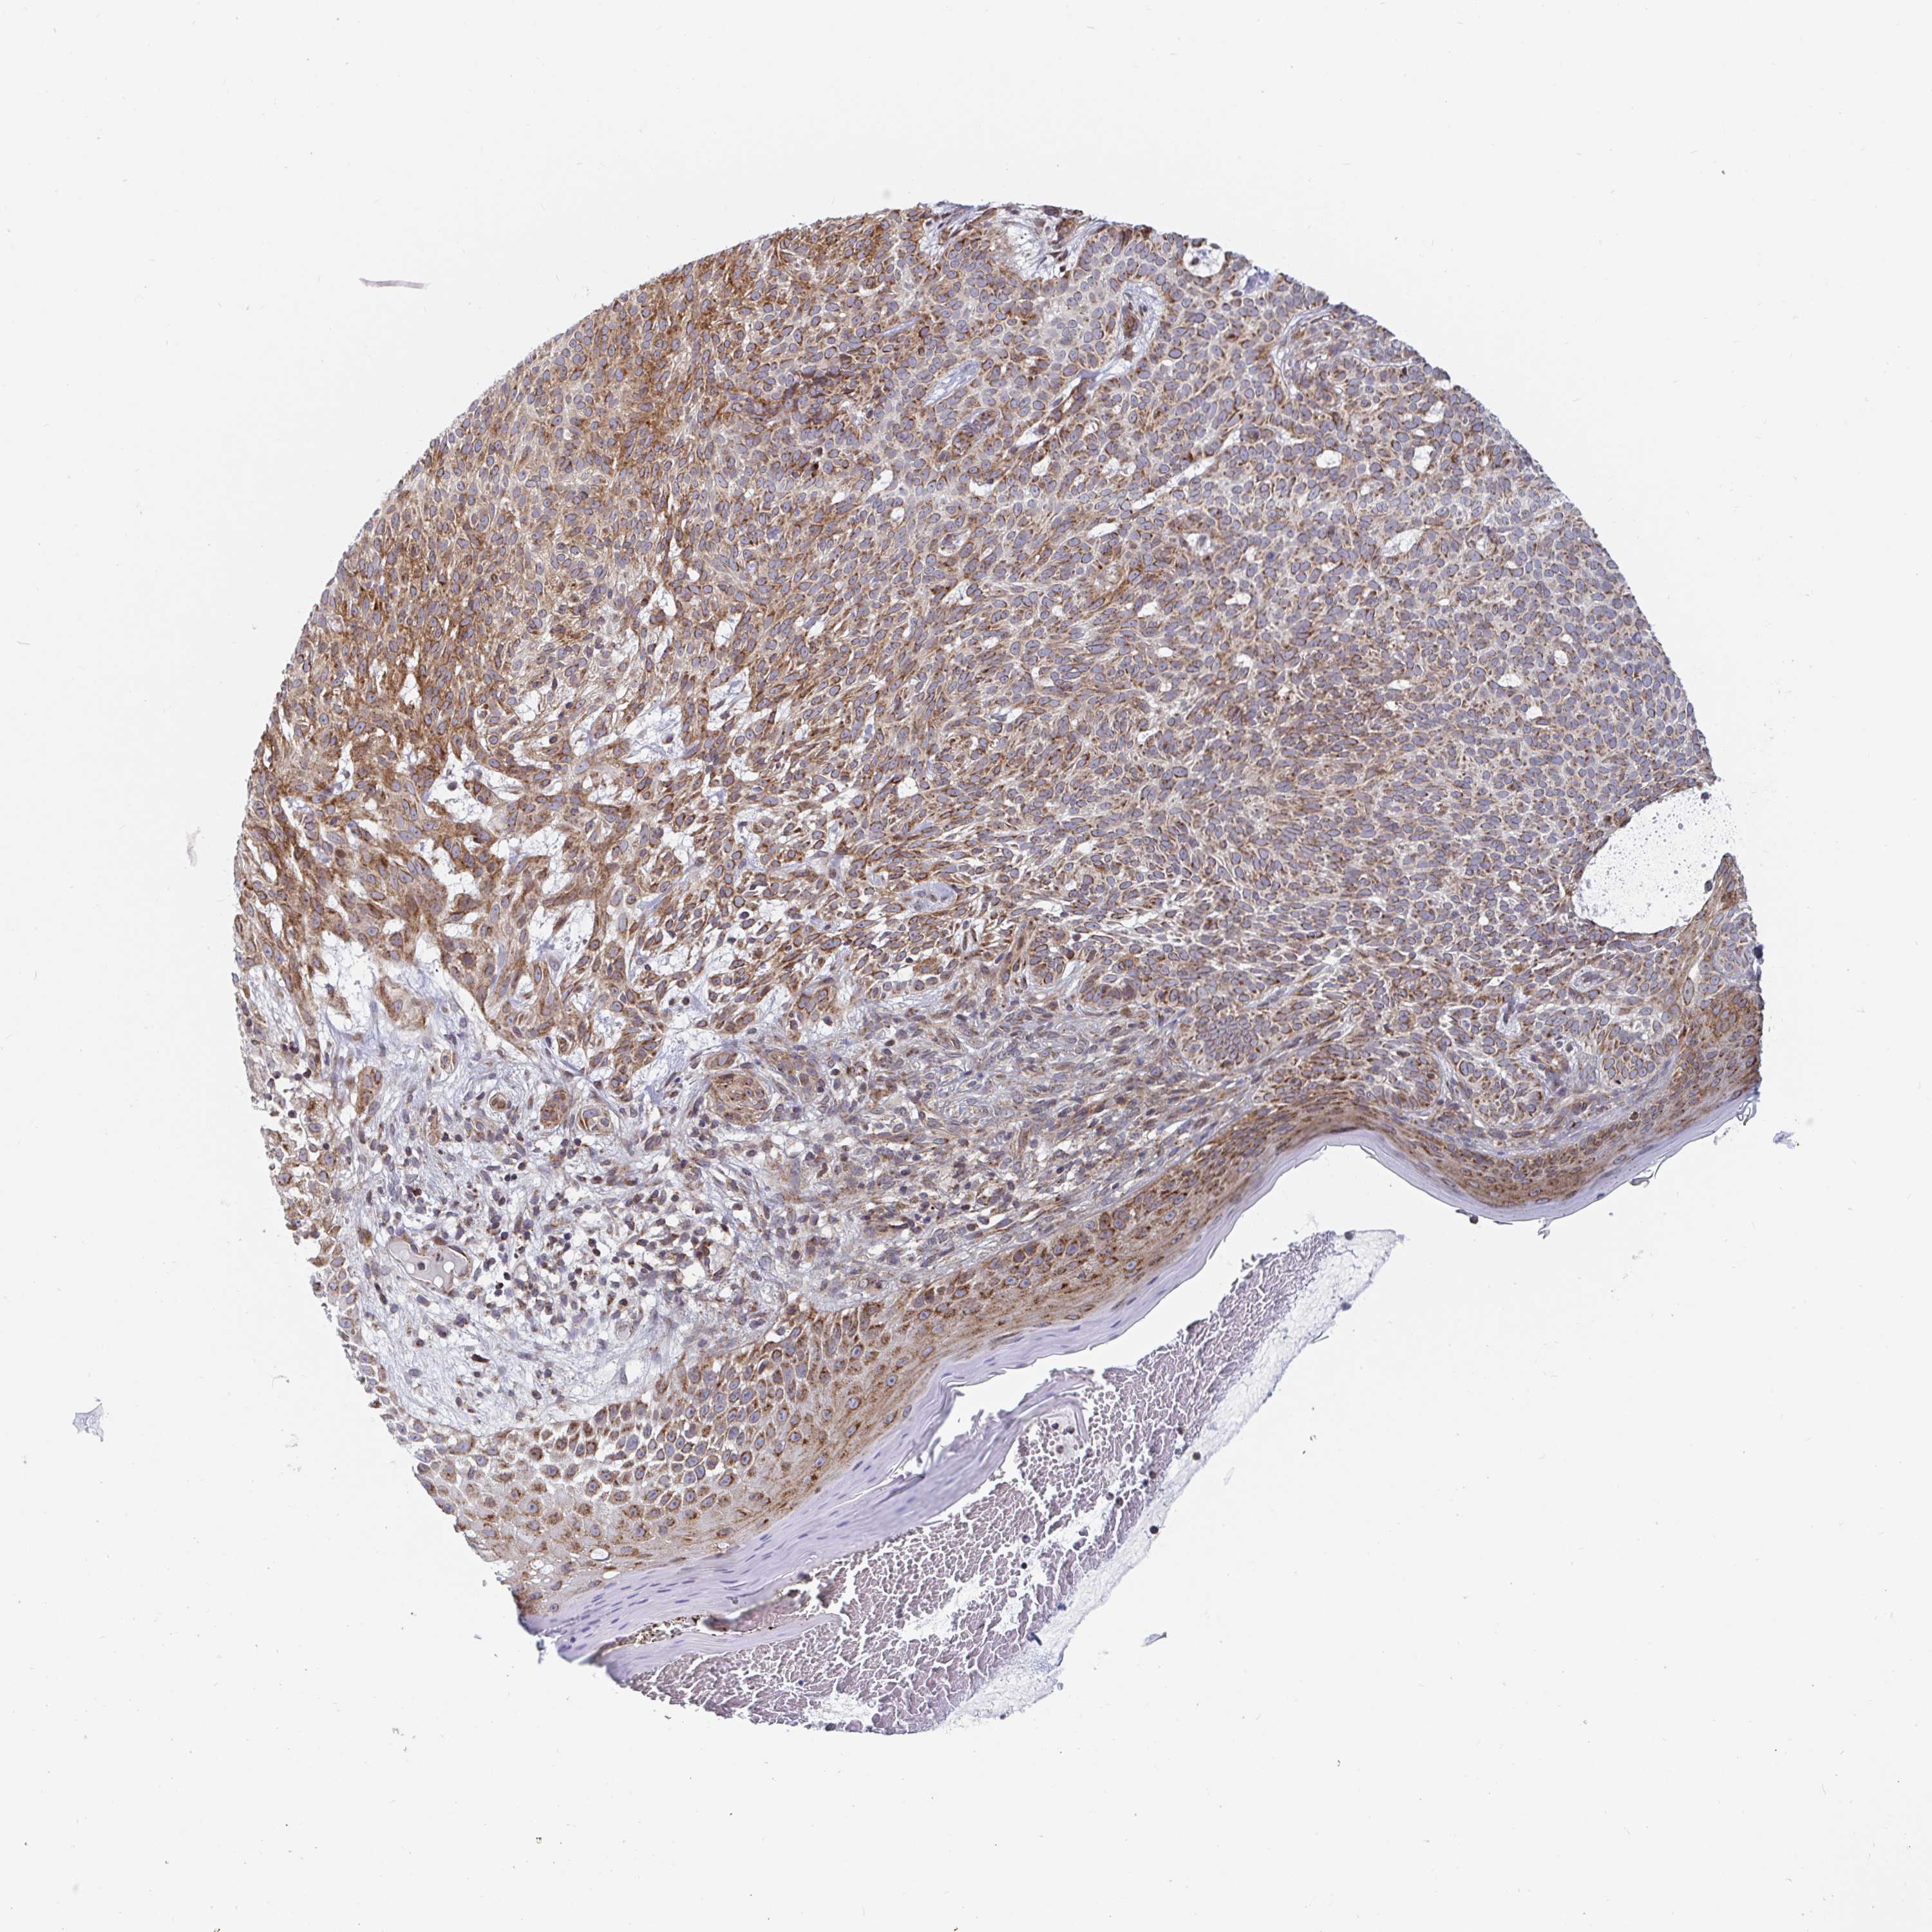

SKIN CANCER - Protein expressioni

A mouse-over function shows sample information and annotation data. Click on an image to view it in a full screen mode. Samples can be filtered based on level of antibody staining by selecting one or several of the following categories: high, medium, low and not detected. The assay and annotation is described here.

Antibody stainingi

Antibody staining in the annotated cell types in the current human tissue is reported as not detected, low, medium, or high, based on conventional immunohistochemistry profiling in selected tissues. This score is based on the combination of the staining intensity and fraction of stained cells.

Each image is clickable and will lead to virtual microscopy that enables deeper exploration of all samples and also displays staining intensity scores, fraction scores and subcellular localization as well as patient and tissue information for each sample.

Antibody HPA060788

Staining

High

Medium

Low

Not detected

Intensity

Strong

Moderate

Weak

Negative

Quantity

>75%

75%-25%

<25%

None

Location

Nuclear

Cytoplasmic/membranous

Cytoplasmic/membranous,nuclear

Basal cell carcinoma

BCC, high aggressive

Squamous cell carcinoma, NOS